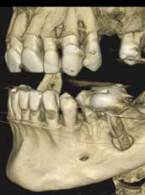

Inwazyjna resorpcja przyszyjkowa zęba 37

Zobacz więcej

lek. stom. Jacek Bilbin